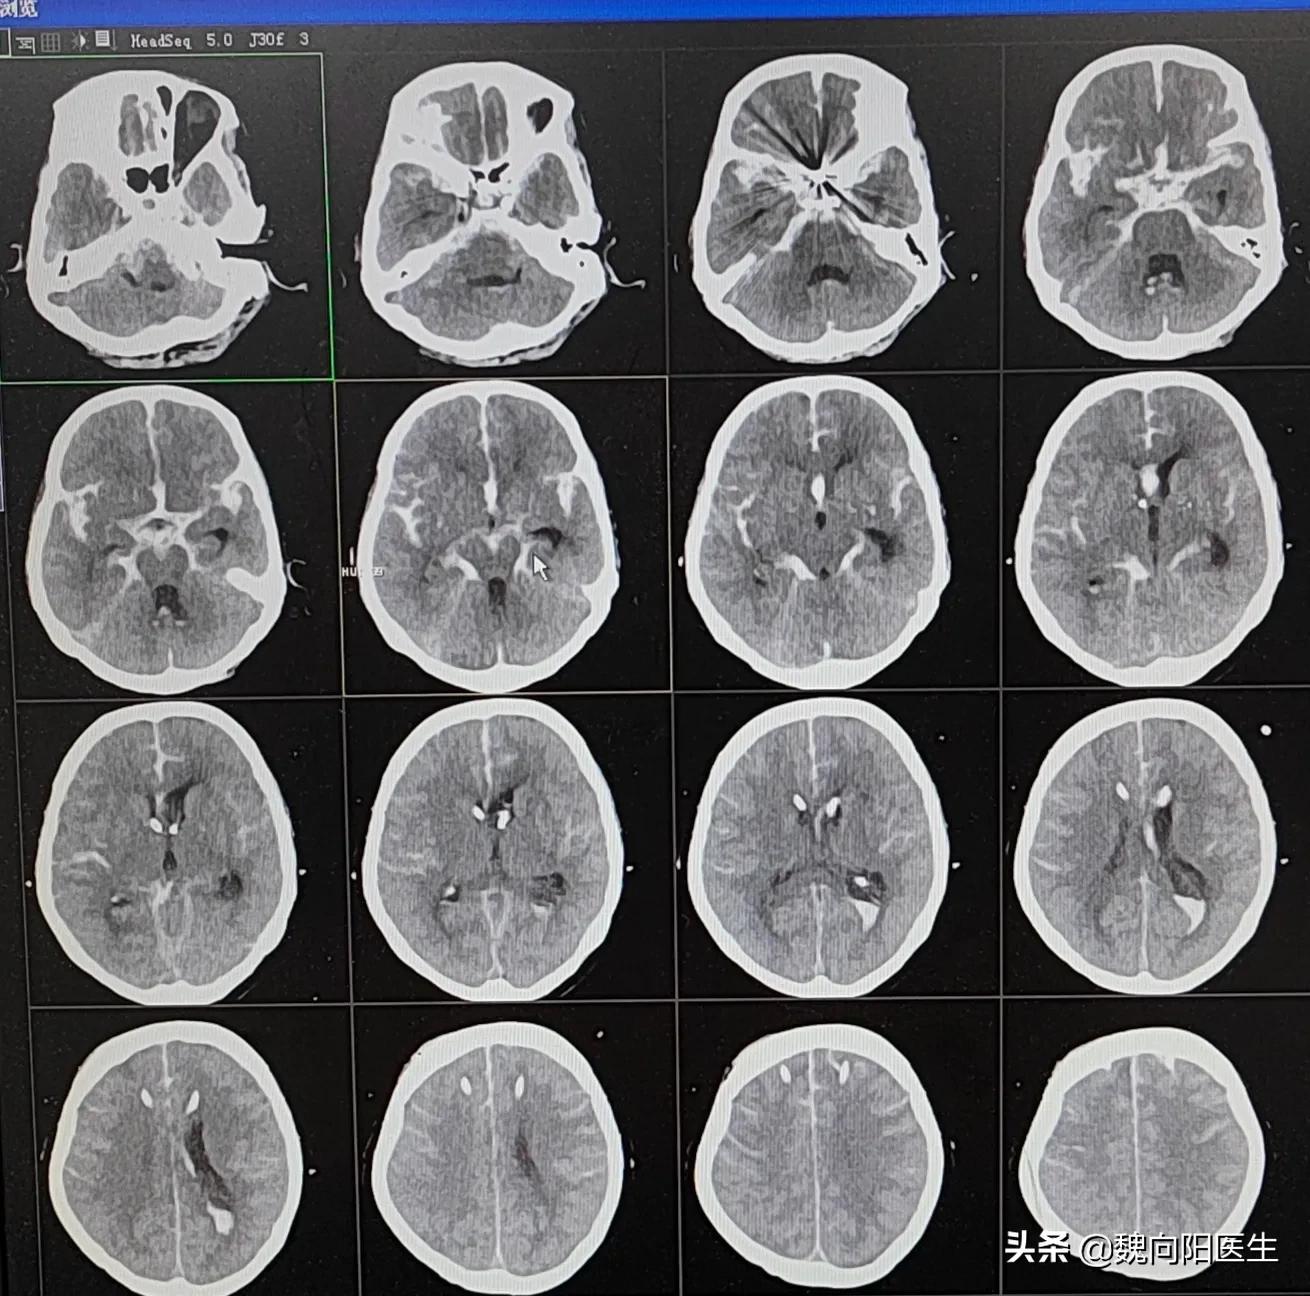

脑出血是一个具有较高的致残性和致死性的神经外科疾病。

而蛛网膜下腔出血是一种特殊的脑出血,大部分的自发性蛛网膜下腔出血都是由于颅内血管瘤破裂导致。

最近连续收治了几例蛛网膜下腔出血的患者,有的救活了,有的没有救活,他们都花费了大量的医疗费用。即使救活的患者,有一半多都遗留了比较严重的后遗症,丧失了继续工作和自我生活的能力。

蛛网膜下腔出血(subarachnoid hemorrhage,SAH)的年发病率为(1~27)/10万,不同地区发病率不同,女性发病率高于男性,且随着年龄的增加而风险增加。

蛛网膜下腔出血引起的头痛,被描述为人一生中所经历的最为严重的头痛,疼痛程度相当剧烈,甚至伴有恶心呕吐。

对于中重度的蛛网膜下腔出血患者死亡率相当高,即使侥幸能够救活,但后期可能会导致严重的残疾,甚至植物人状态。

对于这一类型的蛛网膜下腔出血的患者,早期的治疗费用是相当高的,尤其是没有医保的患者,对于普通家庭来说,绝对是一个天价的医疗费用。